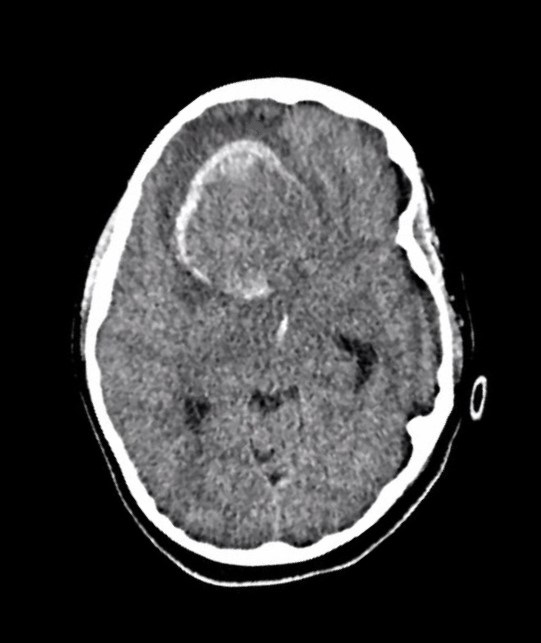

Case_8_CT_non-con.jpg